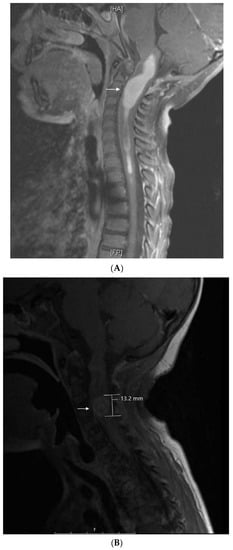

Three months off therapy, she developed a first relapse (Figure 3A) with recurrent tumors in the anterior horn of the left lateral ventricle (two), posterior horn of the left lateral ventricle (one), and anterior horn of the right lateral ventricle (one). CSF showed one abnormal cell. She was treated with 7 weeks of temozolomide followed by 1400 cGy of radiation to the ventricles and Gamma Knife surgery to a residual nodule, followed by autologous peripheral blood stem-cell transplantation (PBSCT), followed by 6 months of isotretinoin.

Figure 3.

Patient 4: (A) image shows and enhancing tumor in the anterior horn of the left ventricle when she presented with first relapse of medulloblastoma. She achieved complete remission with salvage therapy; (B) image shows an enhancing tumor involving the anterior aspect and floor of the fourth ventricle (arrows) when she presented with second relapse; (C) image shows response to 3 months of metronomic therapy with decreased size and intensity of enhancing lesions; (D) image shows interval progression of the tumor seen in T2 FLAIR resulting in a change from temozolomide to etoposide at 4 months of treatment; (E) image shows resolution of the tumor mass and T2 FLAIR changes at 8 months of metronomic therapy; (F) image shows progressive disease at 10 months of treatment.

Three months later, she experienced a second relapse (Figure 3B) with a 1.7 × 1.4 × 0.5 cm enhancing tumor in the fourth ventricle, for which she was started on metronomic chemotherapy with alternating temozolomide (60 mg/m2/day; days 1–21) and CTX (30.9 mg/m2/day; days 22–42), daily celecoxib (250 mg/m2) and VA (15 mg/kg), and bevacizumab (5 mg/kg) every 3 weeks. After 3 months on metronomic chemotherapy (Figure 3C), a partial response was documented with improved enhancing lesions in the dorsal brainstem and inferior vermis. At 4 months (Figure 3D), she developed multiple cranial nerve neuropathies and heterogeneous enhancement with mild increased volume at the left midbrain at the level of the left cerebellar peduncle, for which temozolomide was changed to VP16 (24.6 mg/m2). This was complicated by hematologic toxicity requiring several treatment interruptions and VP16 dose reductions. After 8 months on treatment, MRI showed resolution of the enhancing tumor, an interval decrease in T2 changes, and diffusion restriction in the left cerebellar peduncle (Figure 3E). After 10 months on treatment (Figure 3F), she developed an extensive infiltrative tumor involving the dorsal mesencephalon, pons, and lower brainstem, and she died of her disease 2 months later. This heavily treated patient refractory to aggressive standard salvage therapy experienced 8 months of response and survived 12 months on metronomic chemotherapy.